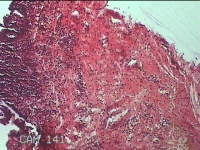

右侧外阴囊肿囊壁

性别

女

年龄

35岁

临床诊断

右侧前庭大腺囊肿

一般病史

发现右侧外阴囊肿1年。

标本名称

大体所见

白暗红色囊性肿物2.3x1.5x0.8cm一个,表面光滑,部分已切开,囊内容物已流失,囊壁厚0.1cm。

良性病变。